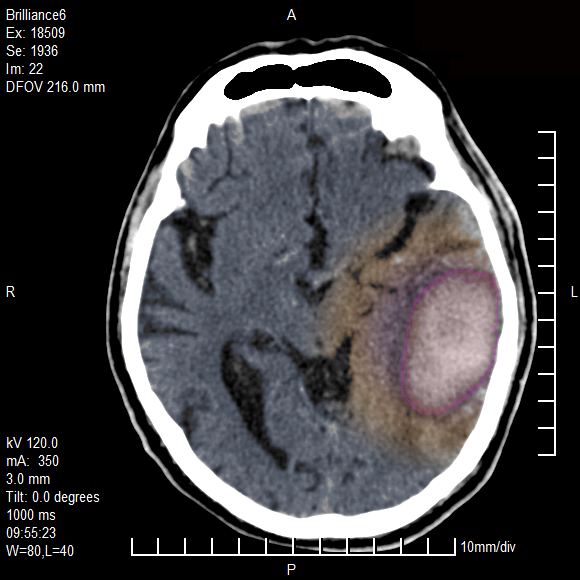

Αυτόματο ενδοεγκεφαλικό αιμάτωμα (κόκκινο περίγραμμα) με περιεστικό οίδημα (μπλέ). Αιμορραγία και στην αριστερή πλάγια κοιλία του εγκεφάλου (πράσινο βέλος). |